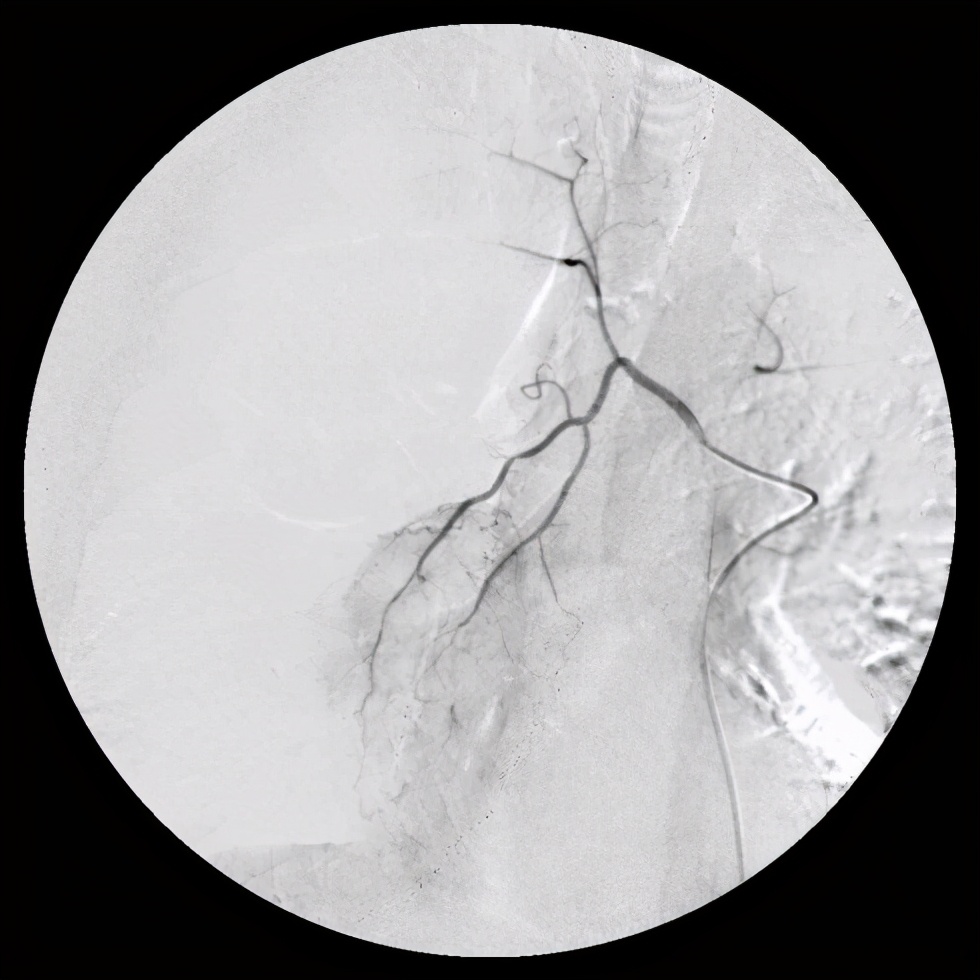

这是做完动脉灌注后的影像,图片来源于网络

通过我们医生的介绍和沟通,坚定了家属们的信心,接下来极力配合我们做患者的工作,最终我们给患者做了支气管动脉灌注治疗。

支气管动脉灌注治疗之前

支气管动脉灌注治疗之后

经过手术后,患者情况得到好转,通过片子我们可以看到分叉的地方肿瘤都变得非常小,虽然没有治愈患者,但是我们用这些手段让病人的痛苦大大的减小生存期也得到了延长,这就是我们治疗的目的,看到患者情况好转,有了很大的恢复,患者儿子告诉我们,这已经超出了他们的预期,虽然没有彻底治愈他的父亲,但是让他们看到希望,给了他们在绝望中一缕曙光,也能够给他们一些陪伴父亲的时间。